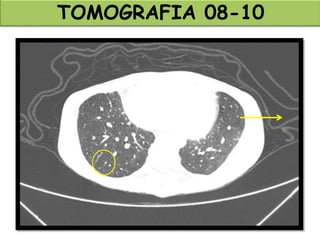

TOMOGRAFIA 08-10

TOMOGRAFIA 28-10